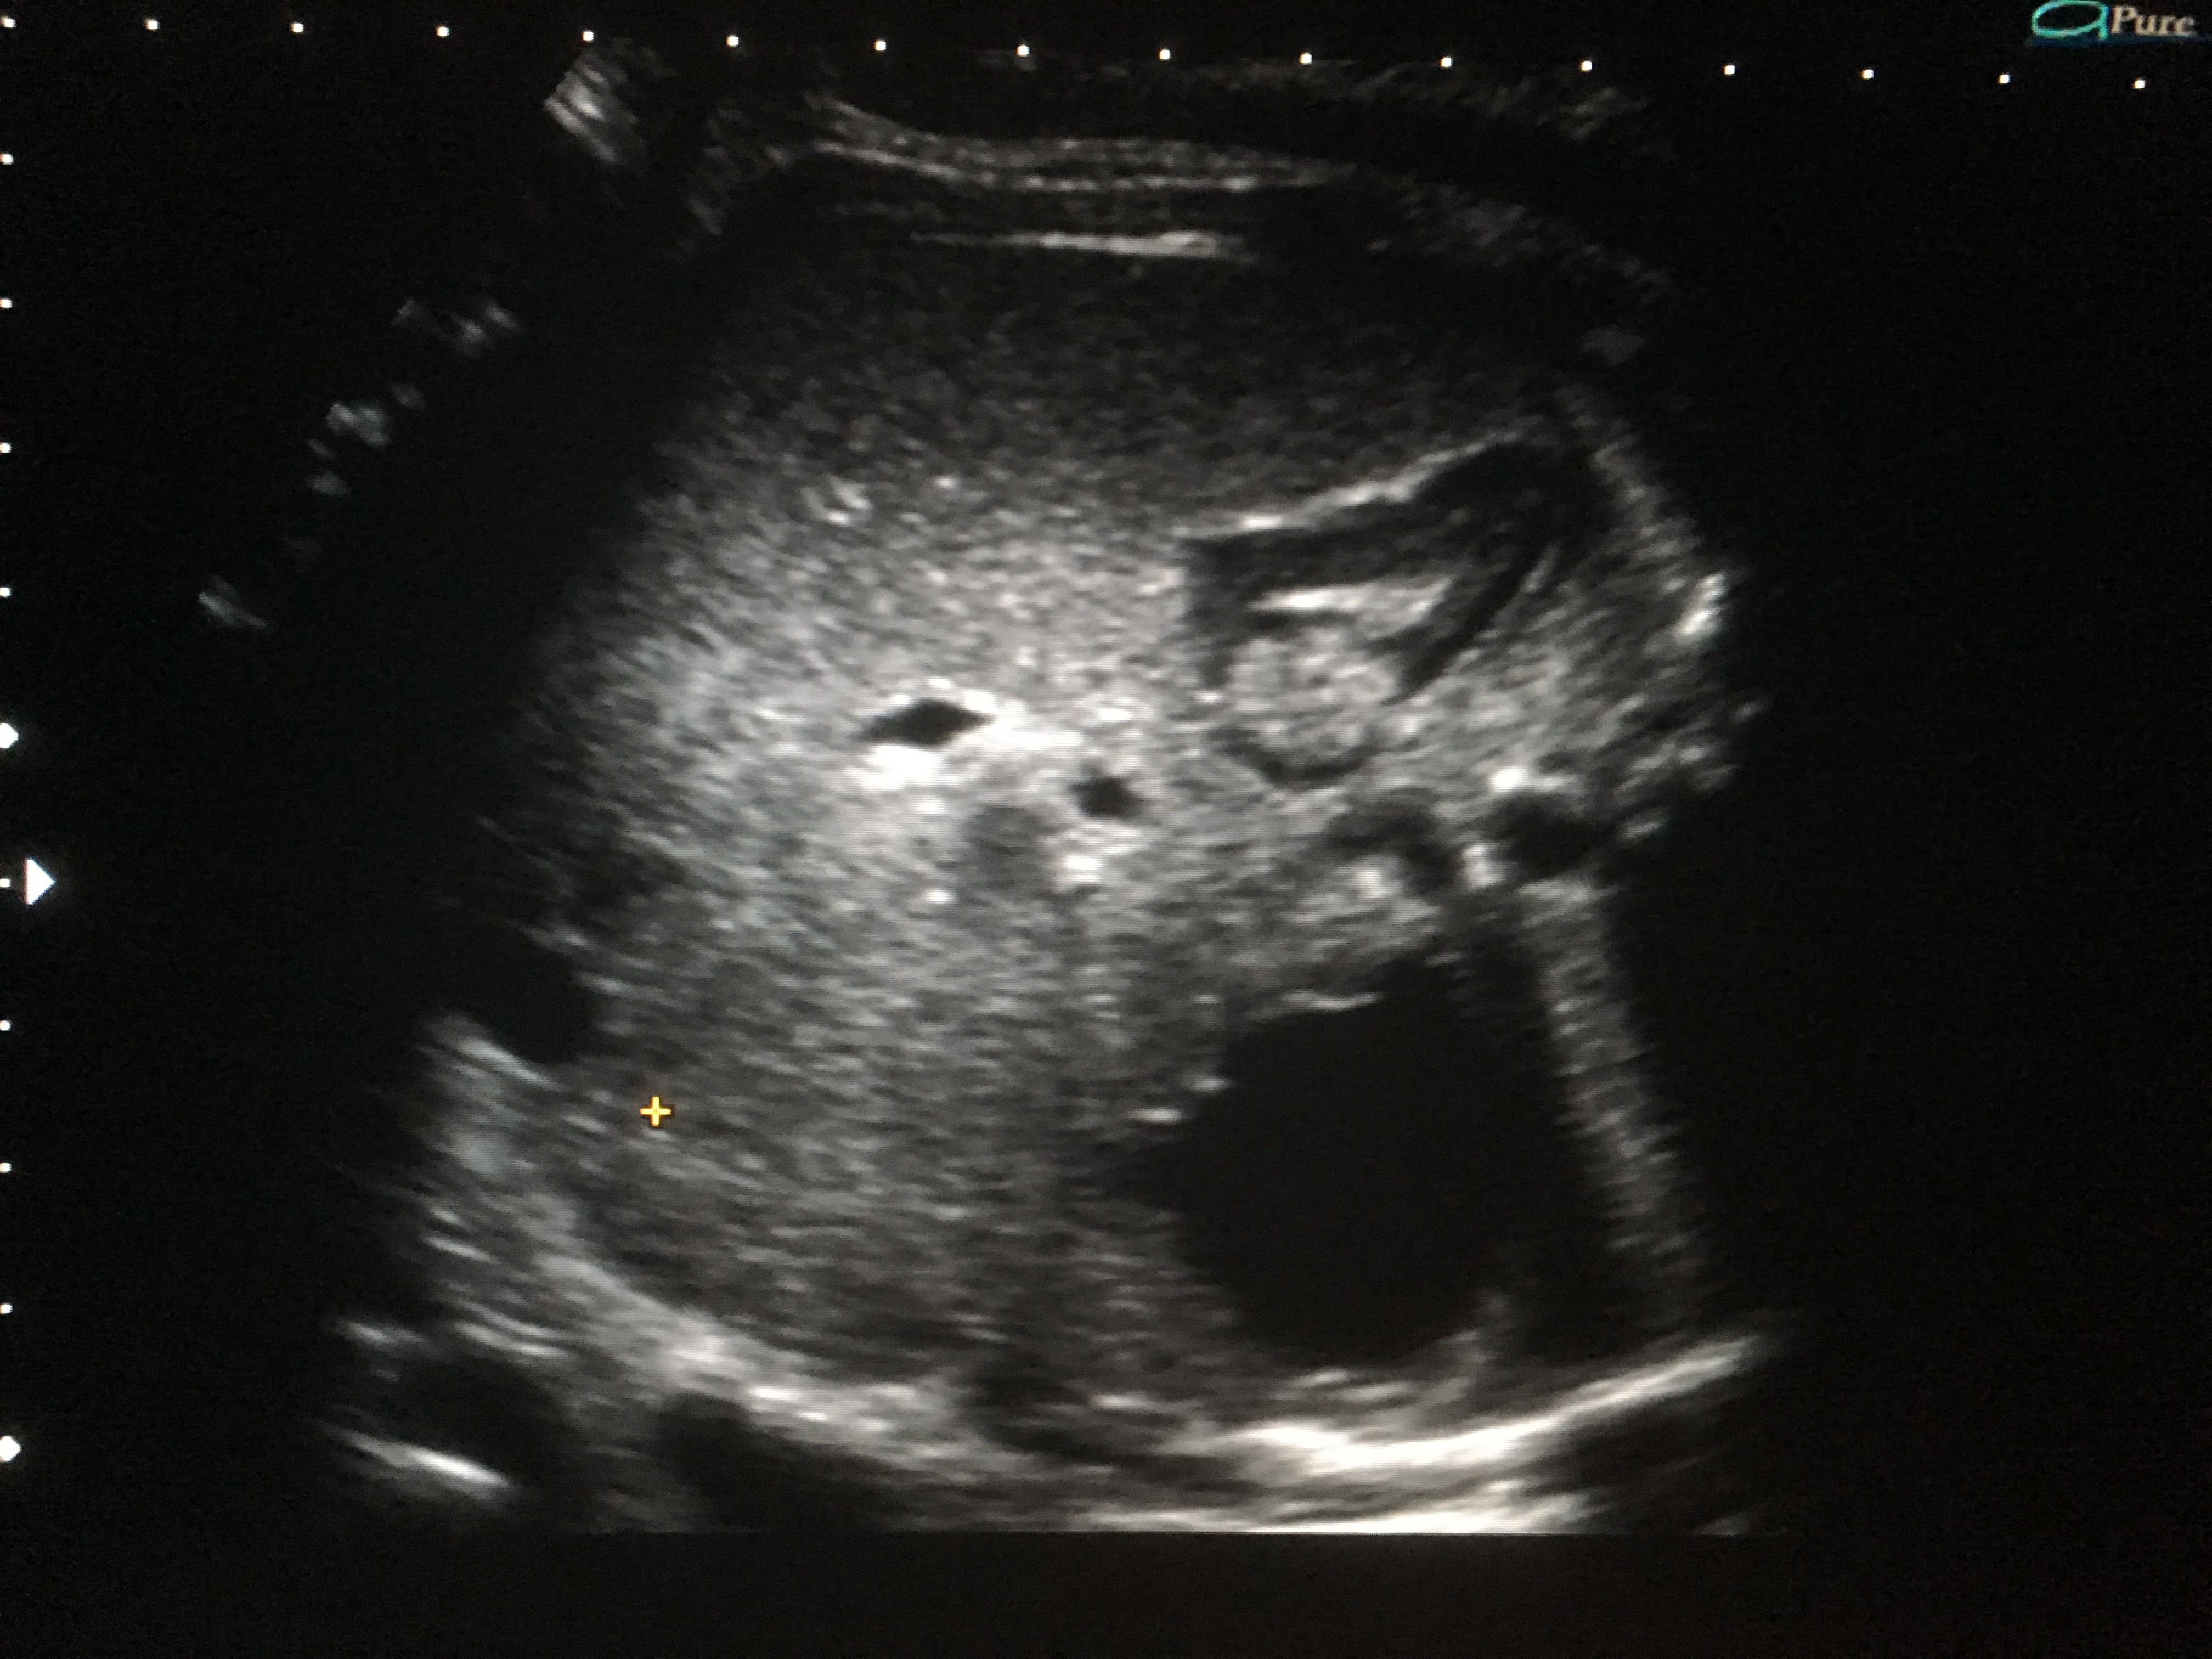

Se presenta a la consulta una paciente primigesta, embarazada de 32 semanas para realizar una ecografía obstétrica de rutina. No presenta antecedentes de relevancia. Se observa la figura 1. Se recita a la paciente a la semana 34 y se observa la figura 2. Fig. 1 - Corte axial a nivel del abdomen fetal. En el hemiabdomen derecho, a nivel posterior, se observa una imagen redondeada, bien circunscripta y ecogénica. Fig. 2 - Corte axial a nivel del abdomen fetal. En el hemiabdomen derecho, a nivel posterior, se observa una imagen redondeada, bien circunscripta, hipoecoica con bordes ecogénicos. ¿Cuál es el diagnóstico más probable? a) Hemorragia suprarrenal derecha b) Neuroblastoma suprarrenal c) Quiste renal derecho

En el caso de las masas adrenales se describen tres aspectos básicos en el ultrasonido. La mitad se expresan como masas sólidas hipoecoicas mientras que el resto se manifiestan ya sea como puramente quísticas o como imágenes complejas con componentes tanto quísticos como sólido. El sangrado adrenal activo se observa ecogénico. Luego en el período de licuefacción suele evolucionar a un aspecto de ecogenicidad mixta o incluso completamente anecoico.

El diagnóstico diferencial más importante es con el neuroblastoma congénito. El neuroblastoma congénito es la neoplasia maligna más frecuente en las glándulas suprarrenales con una incidencia aproximada de 6 cada 1000 recién nacidos vivos. El aspecto ultrasonográfico es muy variado, lo que dificulta su diagnóstico preciso. Mediante ultrasonido y Doppler color es frecuente observar vasos de baja resistencia y alta velocidad que forman una red que involucra a la imagen ultrasonográfica junto con calcificaciones puntiformes. En contraste, en los casos de hemorragia suprarrenal, se suelen observar calcificaciones en forma de anillo y no se detecta flujo sanguíneo con el estudio Doppler.